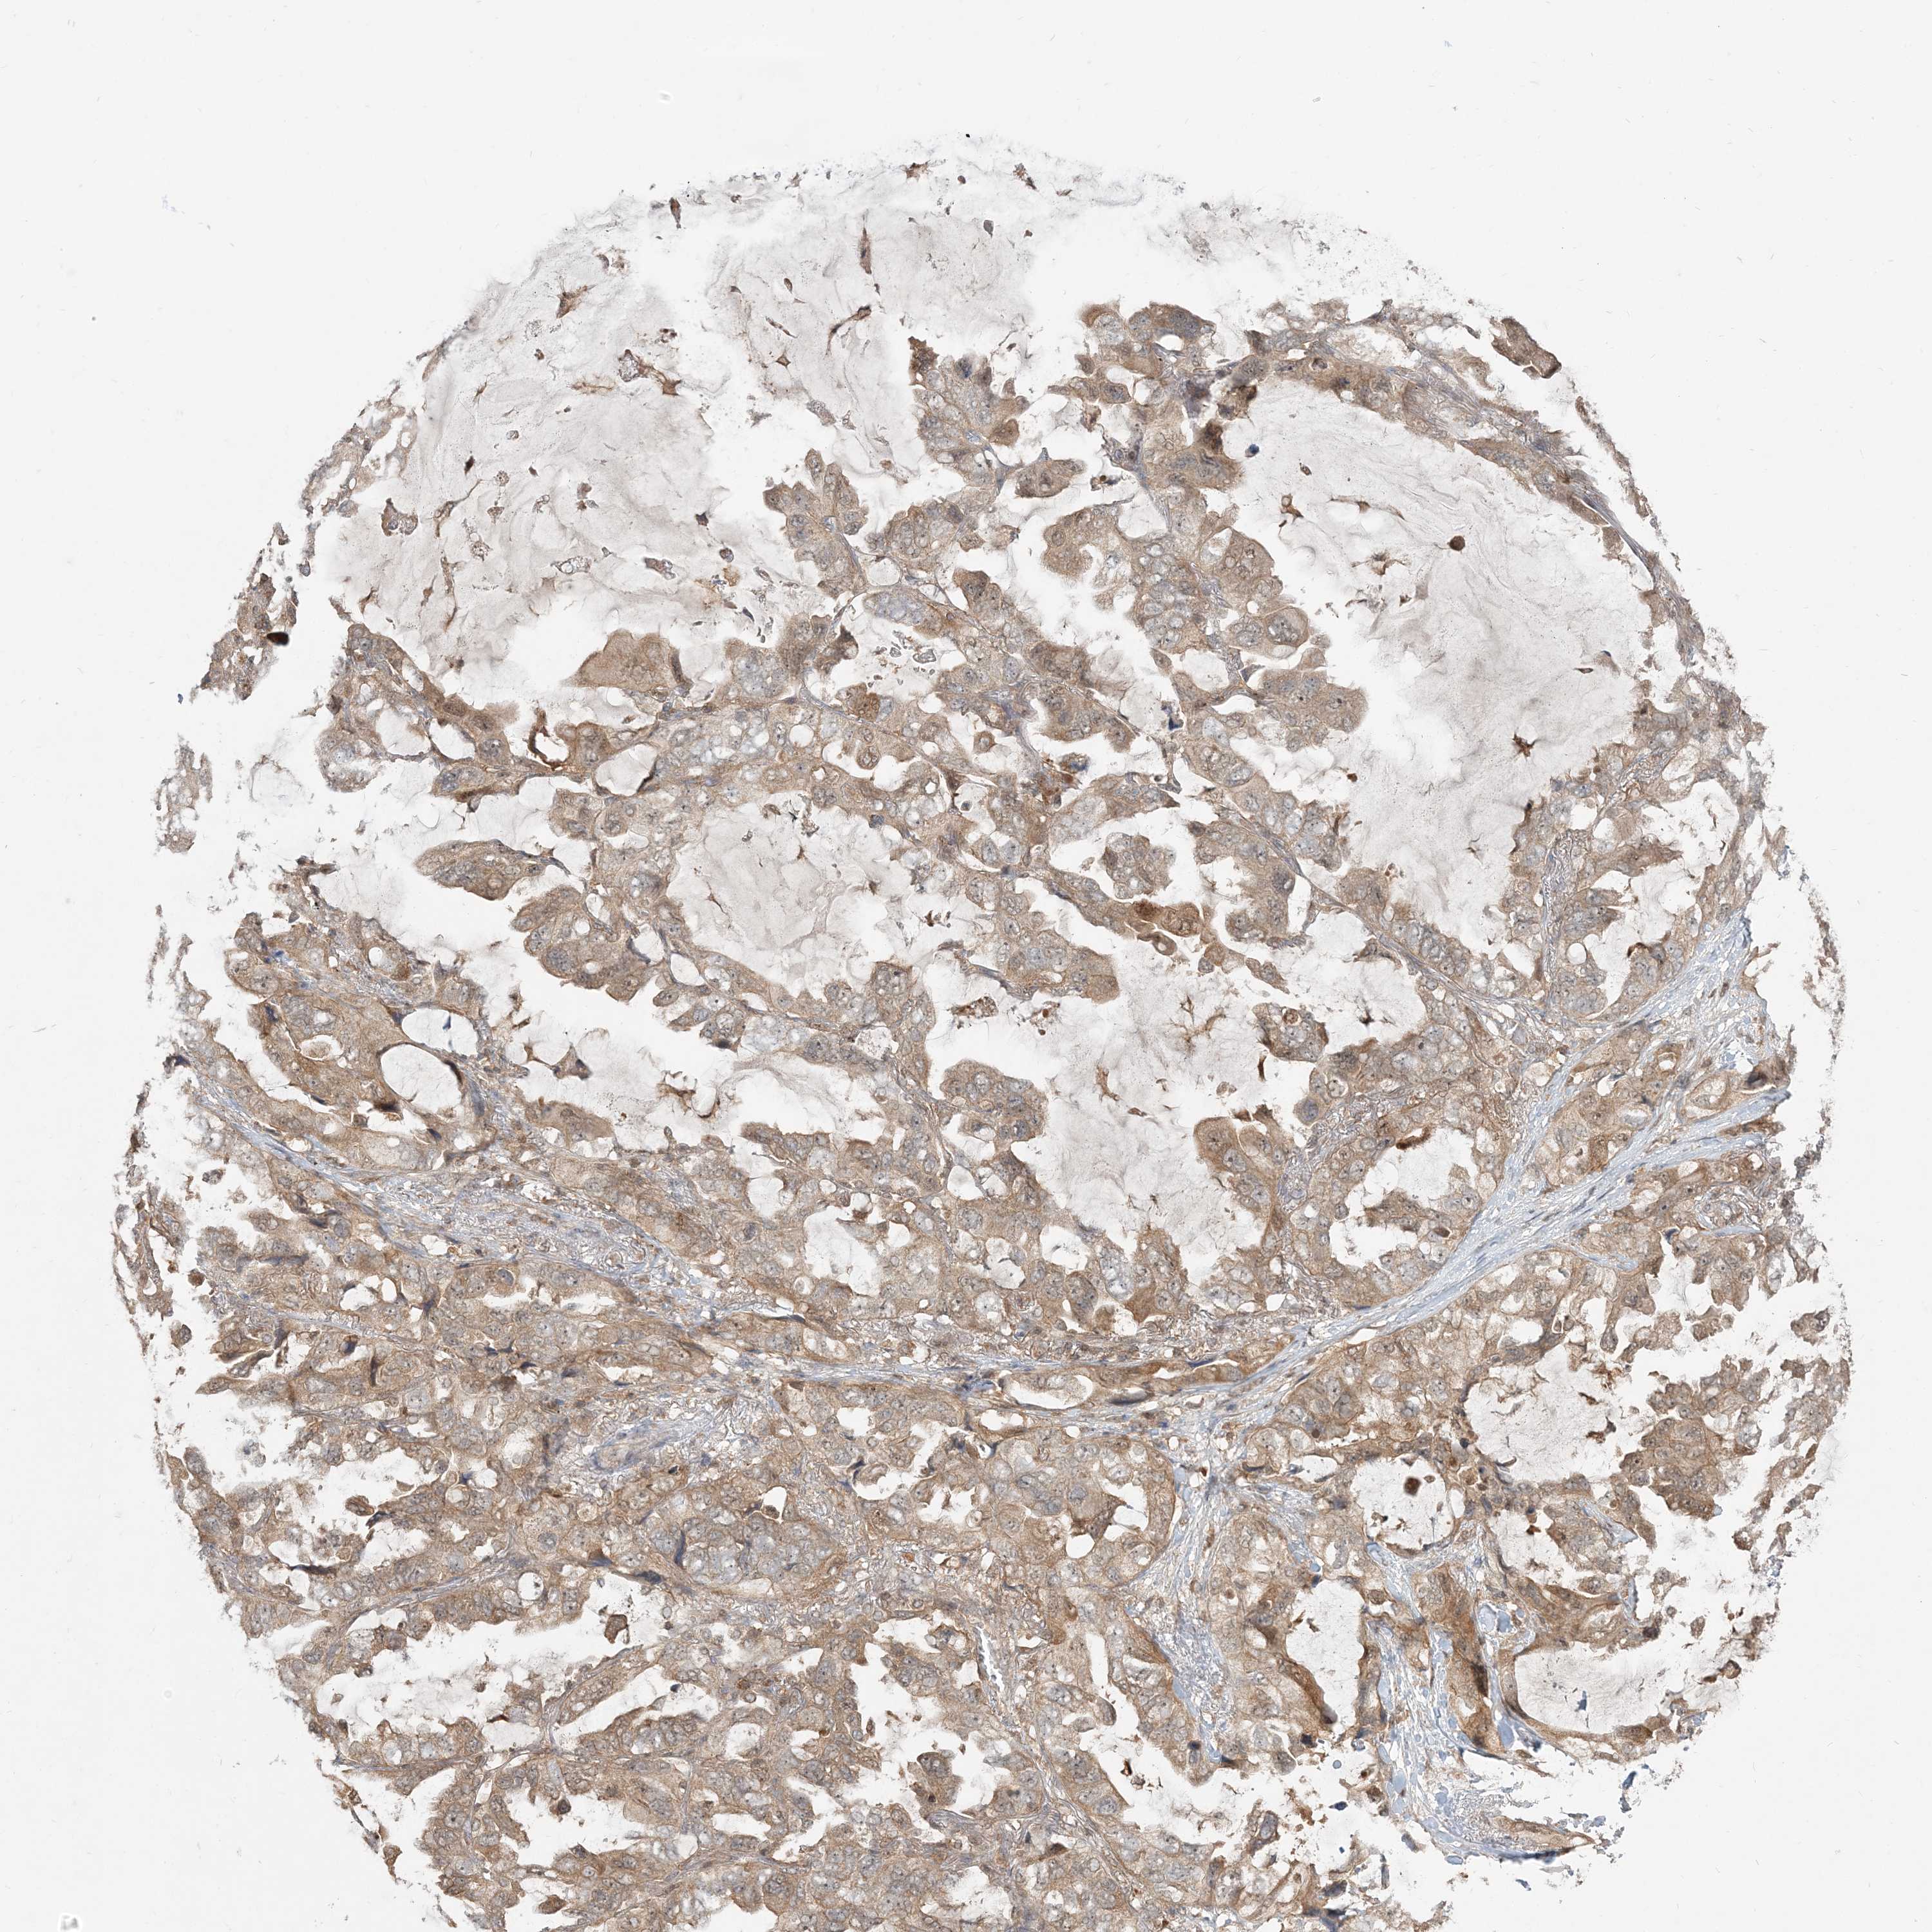

CANCER LUNG CANCER Show tissue menu

LUAD TCGA LUAD VALIDATION LUSC TCGA LUSC VALIDATION PROTEIN LUAD CPTAC PROTEIN LUSC CPTAC PROTEIN EXPRESSION

ANTIBODIES

AND

VALIDATION